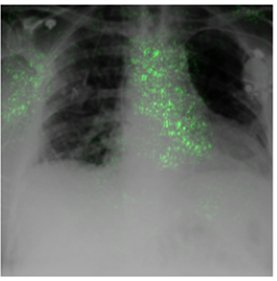

Deep Learning of neural networks has progressively become more prominent in healthcare with models reaching, or even surpassing, expert accuracy levels. However, these success stories are tainted by concerning reports on the lack of model transparency and bias against some medical conditions or patients' sub-groups. Explainable methods are considered the gateway to alleviate many of these concerns. In this study we demonstrate that the generated explanations are volatile to changes in model training that are perpendicular to the classification task and model structure. This raises further questions about trust in deep learning models for healthcare. Mainly, whether the models capture underlying causal links in the data or just rely on spurious correlations that are made visible via explanation methods. We demonstrate that the output of explainability methods on deep neural networks can vary significantly by changes of hyper-parameters, such as the random seed or how the training set is shuffled. We introduce a measure of explanation consistency which we use to highlight the identified problems on the MIMIC-CXR dataset. We find explanations of identical models but with different training setups have a low consistency: $\approx$ 33% on average. On the contrary, kernel methods are robust against any orthogonal changes, with explanation consistency at 94%. We conclude that current trends in model explanation are not sufficient to mitigate the risks of deploying models in real life healthcare applications.